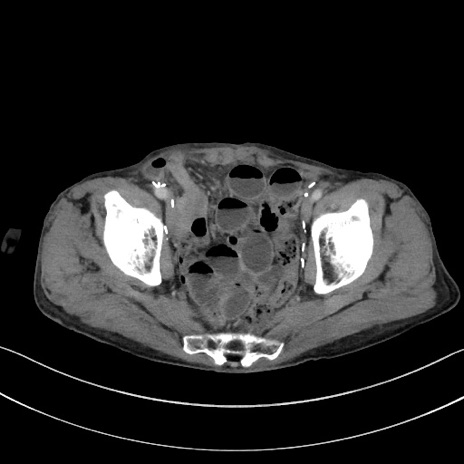

症例3(横断像)

【症例】 70歳代男性

【主訴】右鼠径部腫瘤、疼痛

【現病歴】本日朝より上記主訴あり、受診。

【既往歴】膀胱癌にて膀胱全摘、両側尿管皮膚瘻

【データ】WBC 5600、CRP 0.56